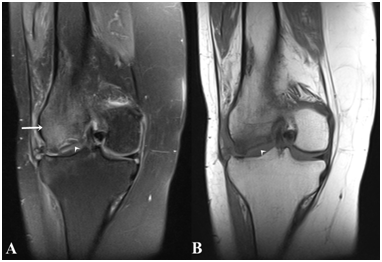

Figure 2 Sagittal reforming CT image shows a hypodense area (arrowhead) at the subchondral level in the lateral condyle of the femur.